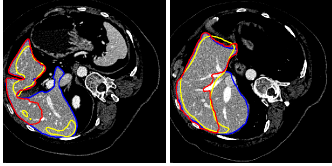

Refer to caption

Figure 6: Illustrations of the role of the likelihood liver map. From the first column to the last, outcomes of graph cut without the likelihood liver map, convolutional neural networks and the proposed integrated model for two typical images are displayed respectively in red. The ground truth is in blue

To better understand the role of the learned liver likelihood map, Fig. 6 depicts the outputs of the graph cut without the liver likelihood map, 3D CNNs and the proposed method for two typical images in red. The ground truth segmentations drawn by experts are in blue. Obviously, incorporated with the liver likelihood map, the proposed model can achieve a better agreement with the ground truth.